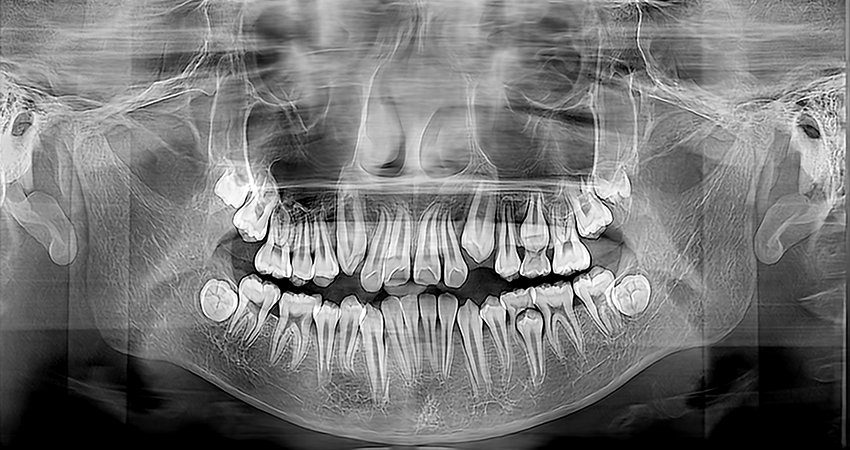

Lateral/Frontal

Algoritmos de Imagen

Potente Funcionalidad